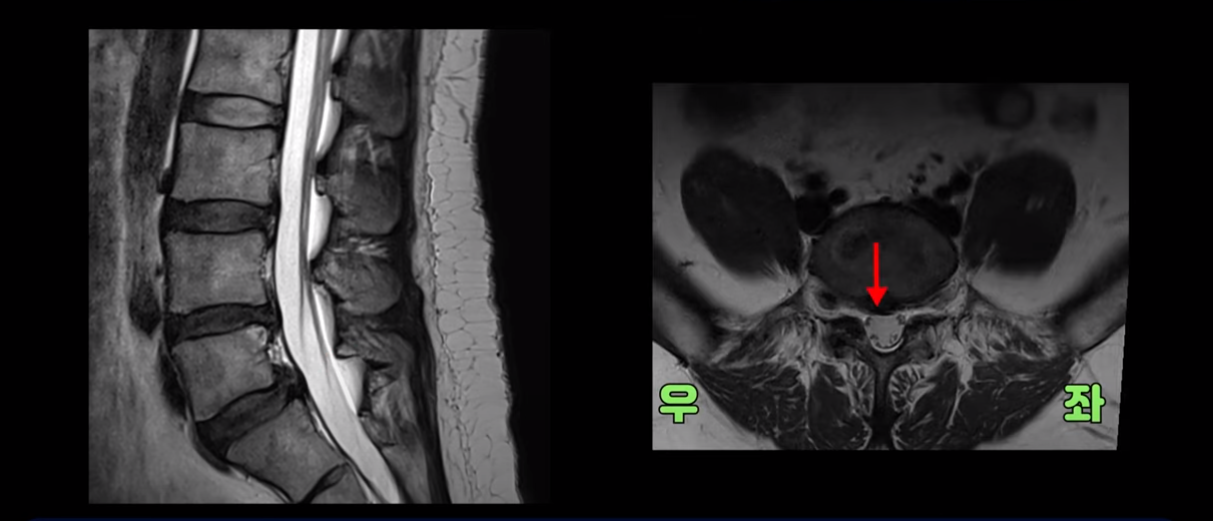

무거운 물건을 들다가 갑자기 심한 허리 통증 및 오른쪽 다리 방사통과 함께 오른쪽 고관절, 무릎, 발목에 운동 마비가 발생했습니다. 왼쪽 다리와 발은 움직이는데 오른쪽 다리와 발은 움직임이 전혀 없습니다. 문제는 이분 MRI를 보면 디스크 탈출이 심해 보이지 않습니다.

가운데 우측으로 파열도 아닌 돌출 정도의 탈출만 있습니다.

추간공도 충분히 열려 있는 상태입니다.

누가 봐도 이 정도 디스크로는 심한 마비가 올 수 없는 상태입니다. 근전도도 정확하게 마비의 원인이 허리에 있다고 설명하지 못했습니다. 그러니까 어느 병원도 수술을 자신 있게 하라고 얘기를 못 하고 마비가 왔으니까 그래도 수술을 해 보는 게 낫지 않겠냐고 얘기합니다.